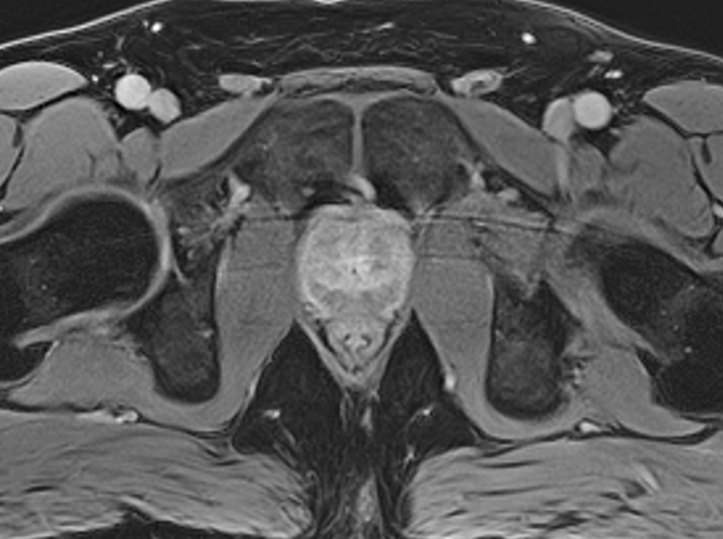

Простата расположена в труднодоступной для диагностики анатомической области, однако метод магнитно-резонансной томографии позволяет детально изучить структуру органа и окружающих ее тканей, включая семенные пузырьки (секреторные органы, вырабатывающие жидкую часть семенной жидкости) и семявыносящие протоки.

При подозрении на опухолевый процесс в предстательной железе в обязательном порядке проводится контрастное усиление. Это подразумевает внутривенное введение контраста, созданного на основе соединений металла гадолиния. Степень и характер накопления контрастного препарата в органах и тканях позволяет различать патологические процессы, в том числе диагностировать опухоли на ранних стадиях, что повышает шансы на успешное лечение.

В клинике «Доступная медицина» диагностика заболеваний предстательной железы выполняется при помощи современного высокопольного магнитно-резонансного томографа экспертного уровня TOSHIBA VANTAGE TITAN 1,5 Тесла. Аппарат производит сканирование в виде послойных тончайших срезов с шагом от 1 мм и преобразует их при помощи инновационных компьютерных программ в изображения трехмерного формата. Методика позволяет получить максимально полную картину о состоянии структуры простаты и окружающих тканей и поставить точный диагноз.